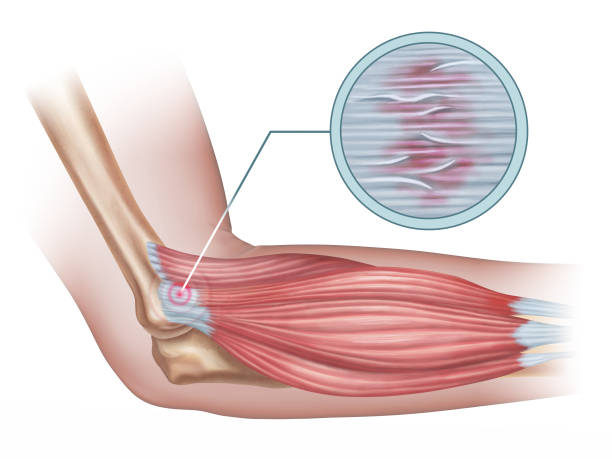

테니스엘보는 테니스엘보라는 이름에 걸맞게 테니스 백핸드 자세에서 팔꿈치 부위에 무리한 힘이 가해지면서 발생하는 팔꿈치 통증으로 정식 진단명은 외측 상과염으로 불립니다. 비단 이 통증은 테니스를 치는 사람에게만 나타나는 것이 아니라 전반적으로 팔을 많이 사용하는 분들에게 나타나며 관리가 잘 되지 않으면 만성질병으로 고착화 될 수 있습니다.

테니스엘보의 증상은 다양한 고통을 수반하는데 우선적으로 팔꿈치 외측에서 통증이 시작해 찌릿찌릿한 통증이 계속됩니다. 덩달아 팔에 힘이 빠지고 심한 경우 쉽게 떨어뜨리게 됩니다. 이러한 통증은 팔꿈치가 지속적으로 아프기 때문에 물건을 잡거나 드는 행위 자체에 고통을 느끼게 됩니다.

테니스엘보는 유래와 마찬가지로 테니스를 치는 분들이 피하기 어려운 질병입니다. 이는 테니스 동작과 비슷한 배드민턴을 치는 분들에게도 자주 일어나는 팔꿈치 통증으로 손목과 팔꿈치에 무리가 됩니다. 물론 테니스나 배드민턴을 치는 분들에게만 일어나는 통증은 아니고 특히 무거운 물건을 자주 드는 분들 혹은 할꿈치를 무리하게 사용하는 운동을 즐기시는 분들에게 많이 발견됩니다.